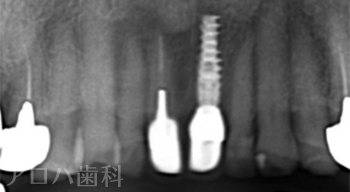

CASE01

初診時

| 主訴 | 入れ歯をやり替えたい |

| 治療内容 | 上下顎とも状態が悪い歯を抜いて奥歯をインプラントで修復しました。 前歯は患者さまの希望のもとそのままにしています。 上顎は骨の高さが足りなかったため、【サイナスリフト】という特殊な手術を行い骨の高さを獲得しています。 術後経過もメインテナンスに通っていただいており、良好な状態を保っています。 |

| 治療期間 | 1年6ヶ月 |

| 治療費用 | 5,060,000円 |

| 費用詳細 | ・サイナスリフト(2か所) 660,000円 ・セデーション(静脈内鎮静法) 110,000円 ・TEC(仮歯) 220,000円 ・インプラント手術+アバットメント+上部構造(9歯) 3,960,000円 ・ポンティック(1歯) 110,000円 |